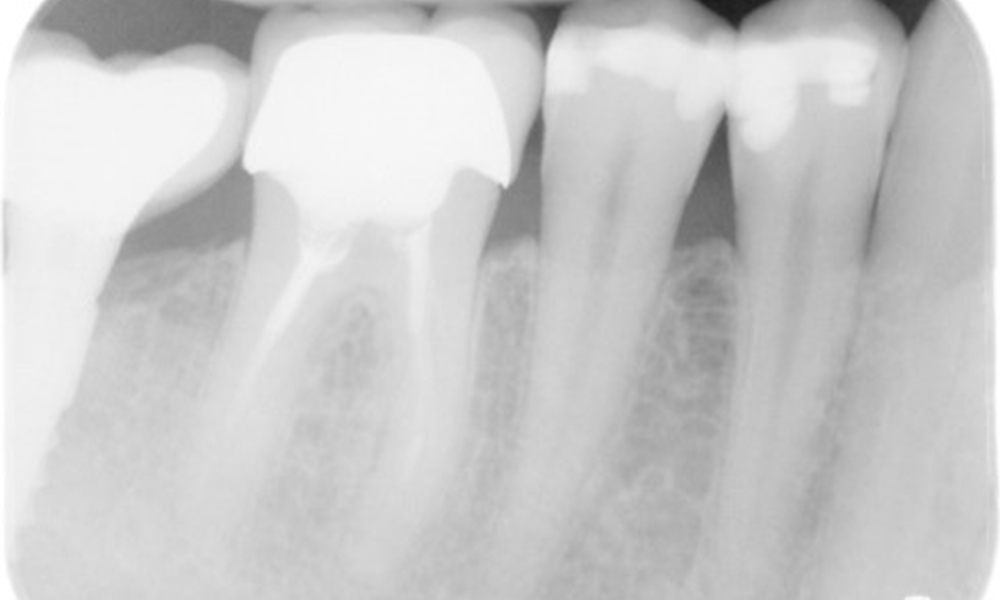

In the medical history, the 55-year-old patient states that he has no systemic disease and is not taking any medication. The patient’s lifestyle is similarly unremarkable. The patient has a few tooth restorations and two implants (2nd and 4th quadrants). On the basis of current findings, gingivitis is identified in an otherwise stable periodontal condition on the reduced periodontium (stage III, grade A).

The patient has no particular risk factors with specific dental implications. The key factor, therefore, is the requirement in terms of oral health. In this respect, good oral health is evident with stable, reduced periodontium. Should evidence of an increase in probe depth compared with the baseline, combined with diffuse bleeding, be found at a check-up appointment, diagnosis using X-ray imaging (dental X-ray) should be undertaken in order to identify peri-implant bone loss at an early stage and intervene accordingly.